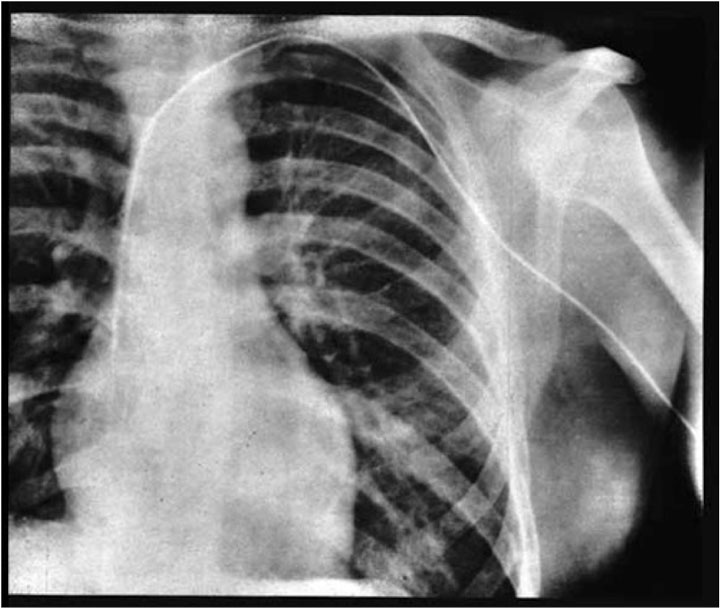

6. Werner Forssmann, qui s’est enfoncé un cathéter dans le coeur

Au début du XIXe siècle, on pensait qu’enfoncer quelque chose dans un coeur battant causerait directement la mort de la personne. Werner Forssmann, lui, était persuadé de l’inverse. Ainsi, en 1929, cet Allemand interne en chirurgie s’est anesthésié le bras pour y insérer une veine allant jusqu’à son corps. Pour vérifier que l’objet avait bien atteint son palpitant, il a vérifié à travers une radio. Cet acte lui aura valu de perdre son travail (mais pas sa vie)… En 1956 cependant, il a reçu un Prix Nobel récompensant sa bravoure.